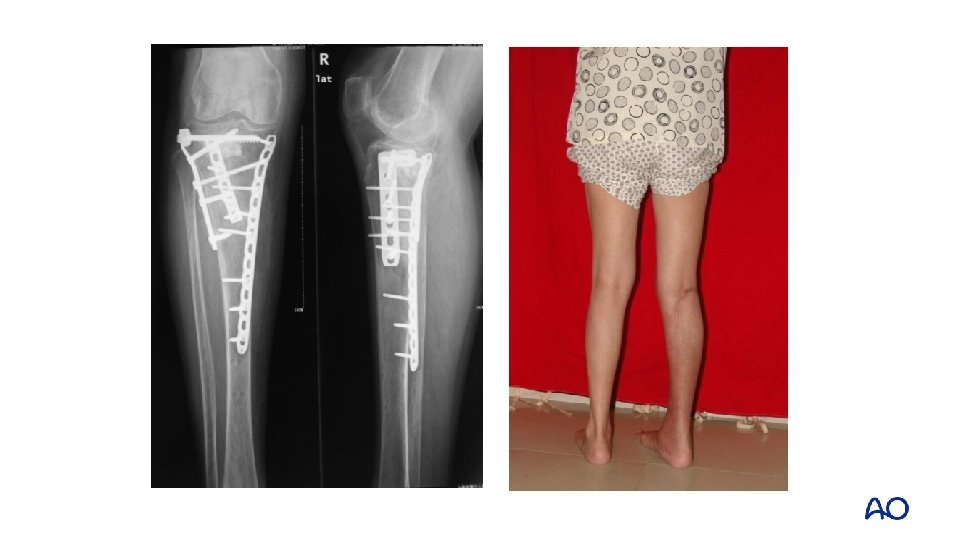

Schatzker type IV: 2 -column fracture—flexion varus Varus flexion mechanism medial posterior

Approach: midline and posteromedial

Midline approach Fracture window Posteromedial approach

1 -year follow up